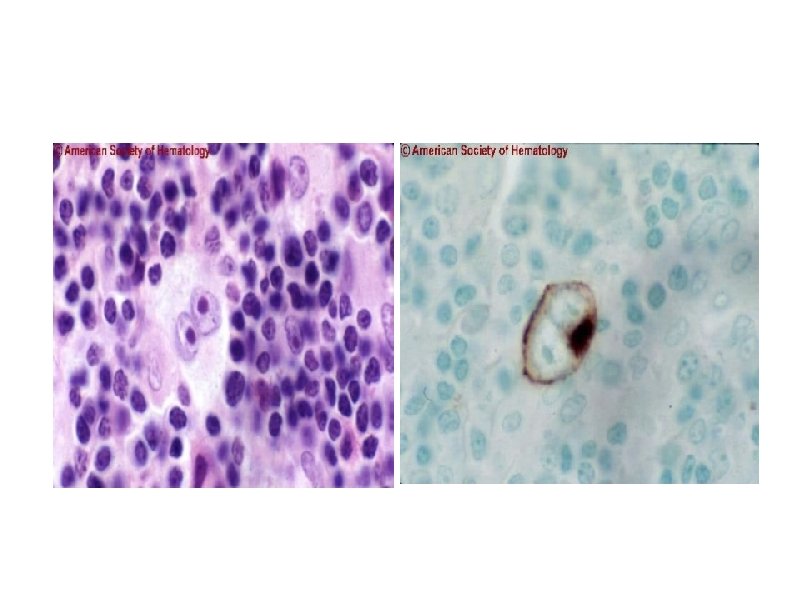

Атипичный лимфоцит (клетка Сезари)

Морфологические варианты лимфогрануломатоза